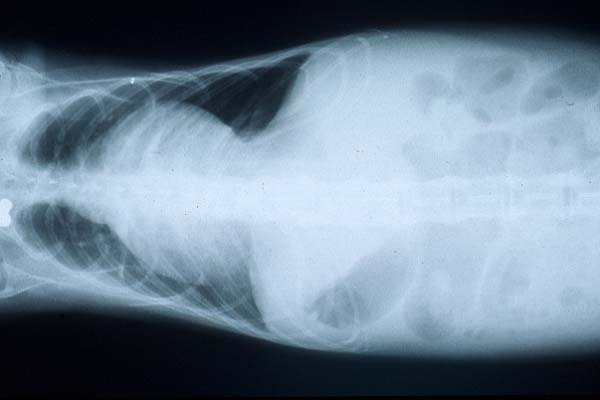

- Case 20-4. Lateral and Dorsal Radiographs. The lateral

view shows diffuse fluid density of the lung space (pulmonary

edema). Both views demonstrate an enlarged cardiac silhouette.

to have a gallop rhythm. Thoracic radiographs revealed an enlarged

cardiac silhouette, compatible with generalized cardiomegaly.

An ECG revealed increased P wave amplitude compatible with right

atrial enlargement, and increased PR interval consistent with